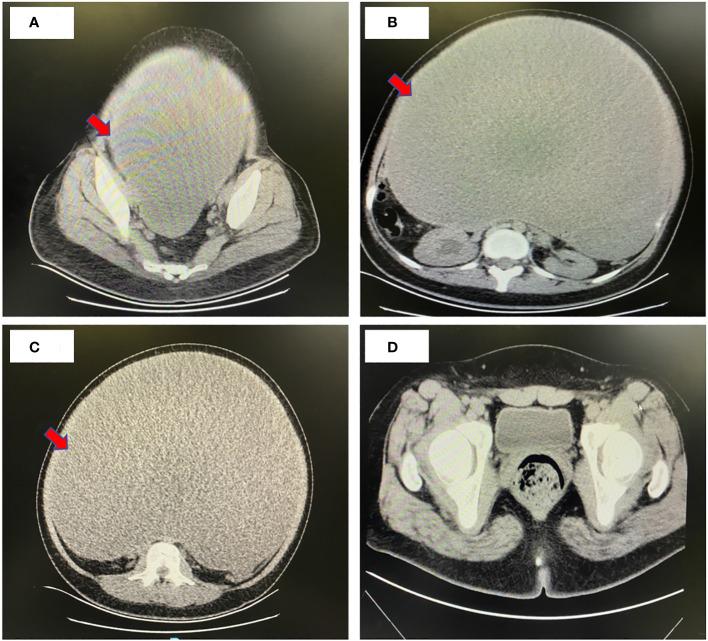

In April 2023, we successfully treated a 21-year-old patient afflicted with a rare giant cystadenocarcinoma, an extraordinarily large mucinous ovarian tumor that weighed nearly 25 kg. The preoperative dimensions of the tumor measured 40 × 30 × 34 cm, with the tumor's weight nearing 25 kg. Despite its uncommon nature, we elected to perform a right adnexectomy, greater omentectomy, and peritoneal biopsy during the surgical intervention due to the patient's youth and the family's expressed desire to preserve fertility. In the subsequent August follow-up, CT scans revealed the complete resolution of the tumor, accompanied by the normalization of tumor markers, indicating a favorable outcome.

2023年4月,我们成功治疗了一名21岁患有罕见巨大囊腺癌的患者,这是一种极其大的黏液性卵巢肿瘤,重达近25千克。肿瘤术前尺寸为40×30×34厘米,重量接近25千克。尽管其性质罕见,但由于患者年轻且家属表示希望保留生育能力,我们在手术干预期间选择进行了右侧附件切除术、大网膜切除术和腹膜活检。在随后8月的随访中,CT扫描显示肿瘤完全消退,同时肿瘤标志物恢复正常,表明预后良好。